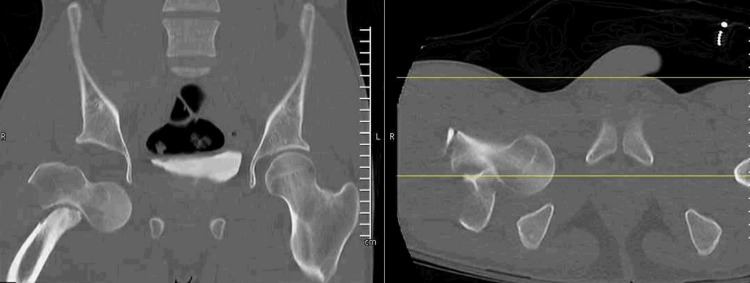

Direct inferior hip dislocation is the rarest type, sometimes referred to as luxatio erecta. To the author's knowledge, an adult inferior hip dislocation with an associated displaced intertrochanteric fracture has only been reported once in the literature. Accordingly, there are few described treatment options for this injury. An 18-year-old male presented after a motor vehicle collision with an inferior hip dislocation and an associated ipsilateral intertrochanteric hip fracture. He was taken to the operating room urgently for the reduction of the dislocation and definitive treatment. In this case, a fracture table was utilized along with a Schanz pin to reduce the hip dislocation and for the reduction and intramedullary nailing of his intertrochanteric fracture.

Abstract Image